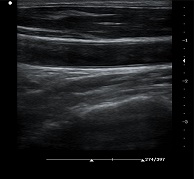

? ? ? ?C7為深圳安盛生物醫(yī)療技術(shù)有限公司新一代便攜式彩超產(chǎn)品,采用了先進(jìn)的PC平臺(tái),擁有強(qiáng)大的處理能力,優(yōu)異的圖像性能,集小巧輕便、全面的功能與輕巧流暢、特有的U型設(shè)計(jì)與一身,提供大眾新選擇。

支持凸陣、線陣、腔內(nèi)、相控陣、小微凸等探頭

? ?● 血管內(nèi)中膜自動(dòng)測(cè)量

? ? ? ?操作簡(jiǎn)單,提高工作效率